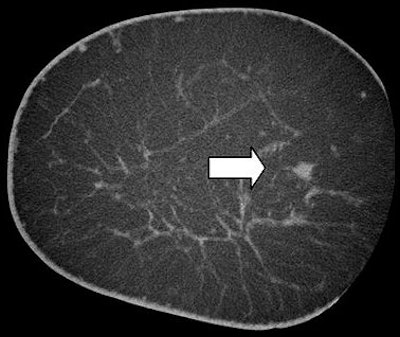

![]() |

| Breast CT shows an ill-defined mass (ductal carcinoma in situ [DCIS]). Image courtesy of John Boone, Ph.D. |